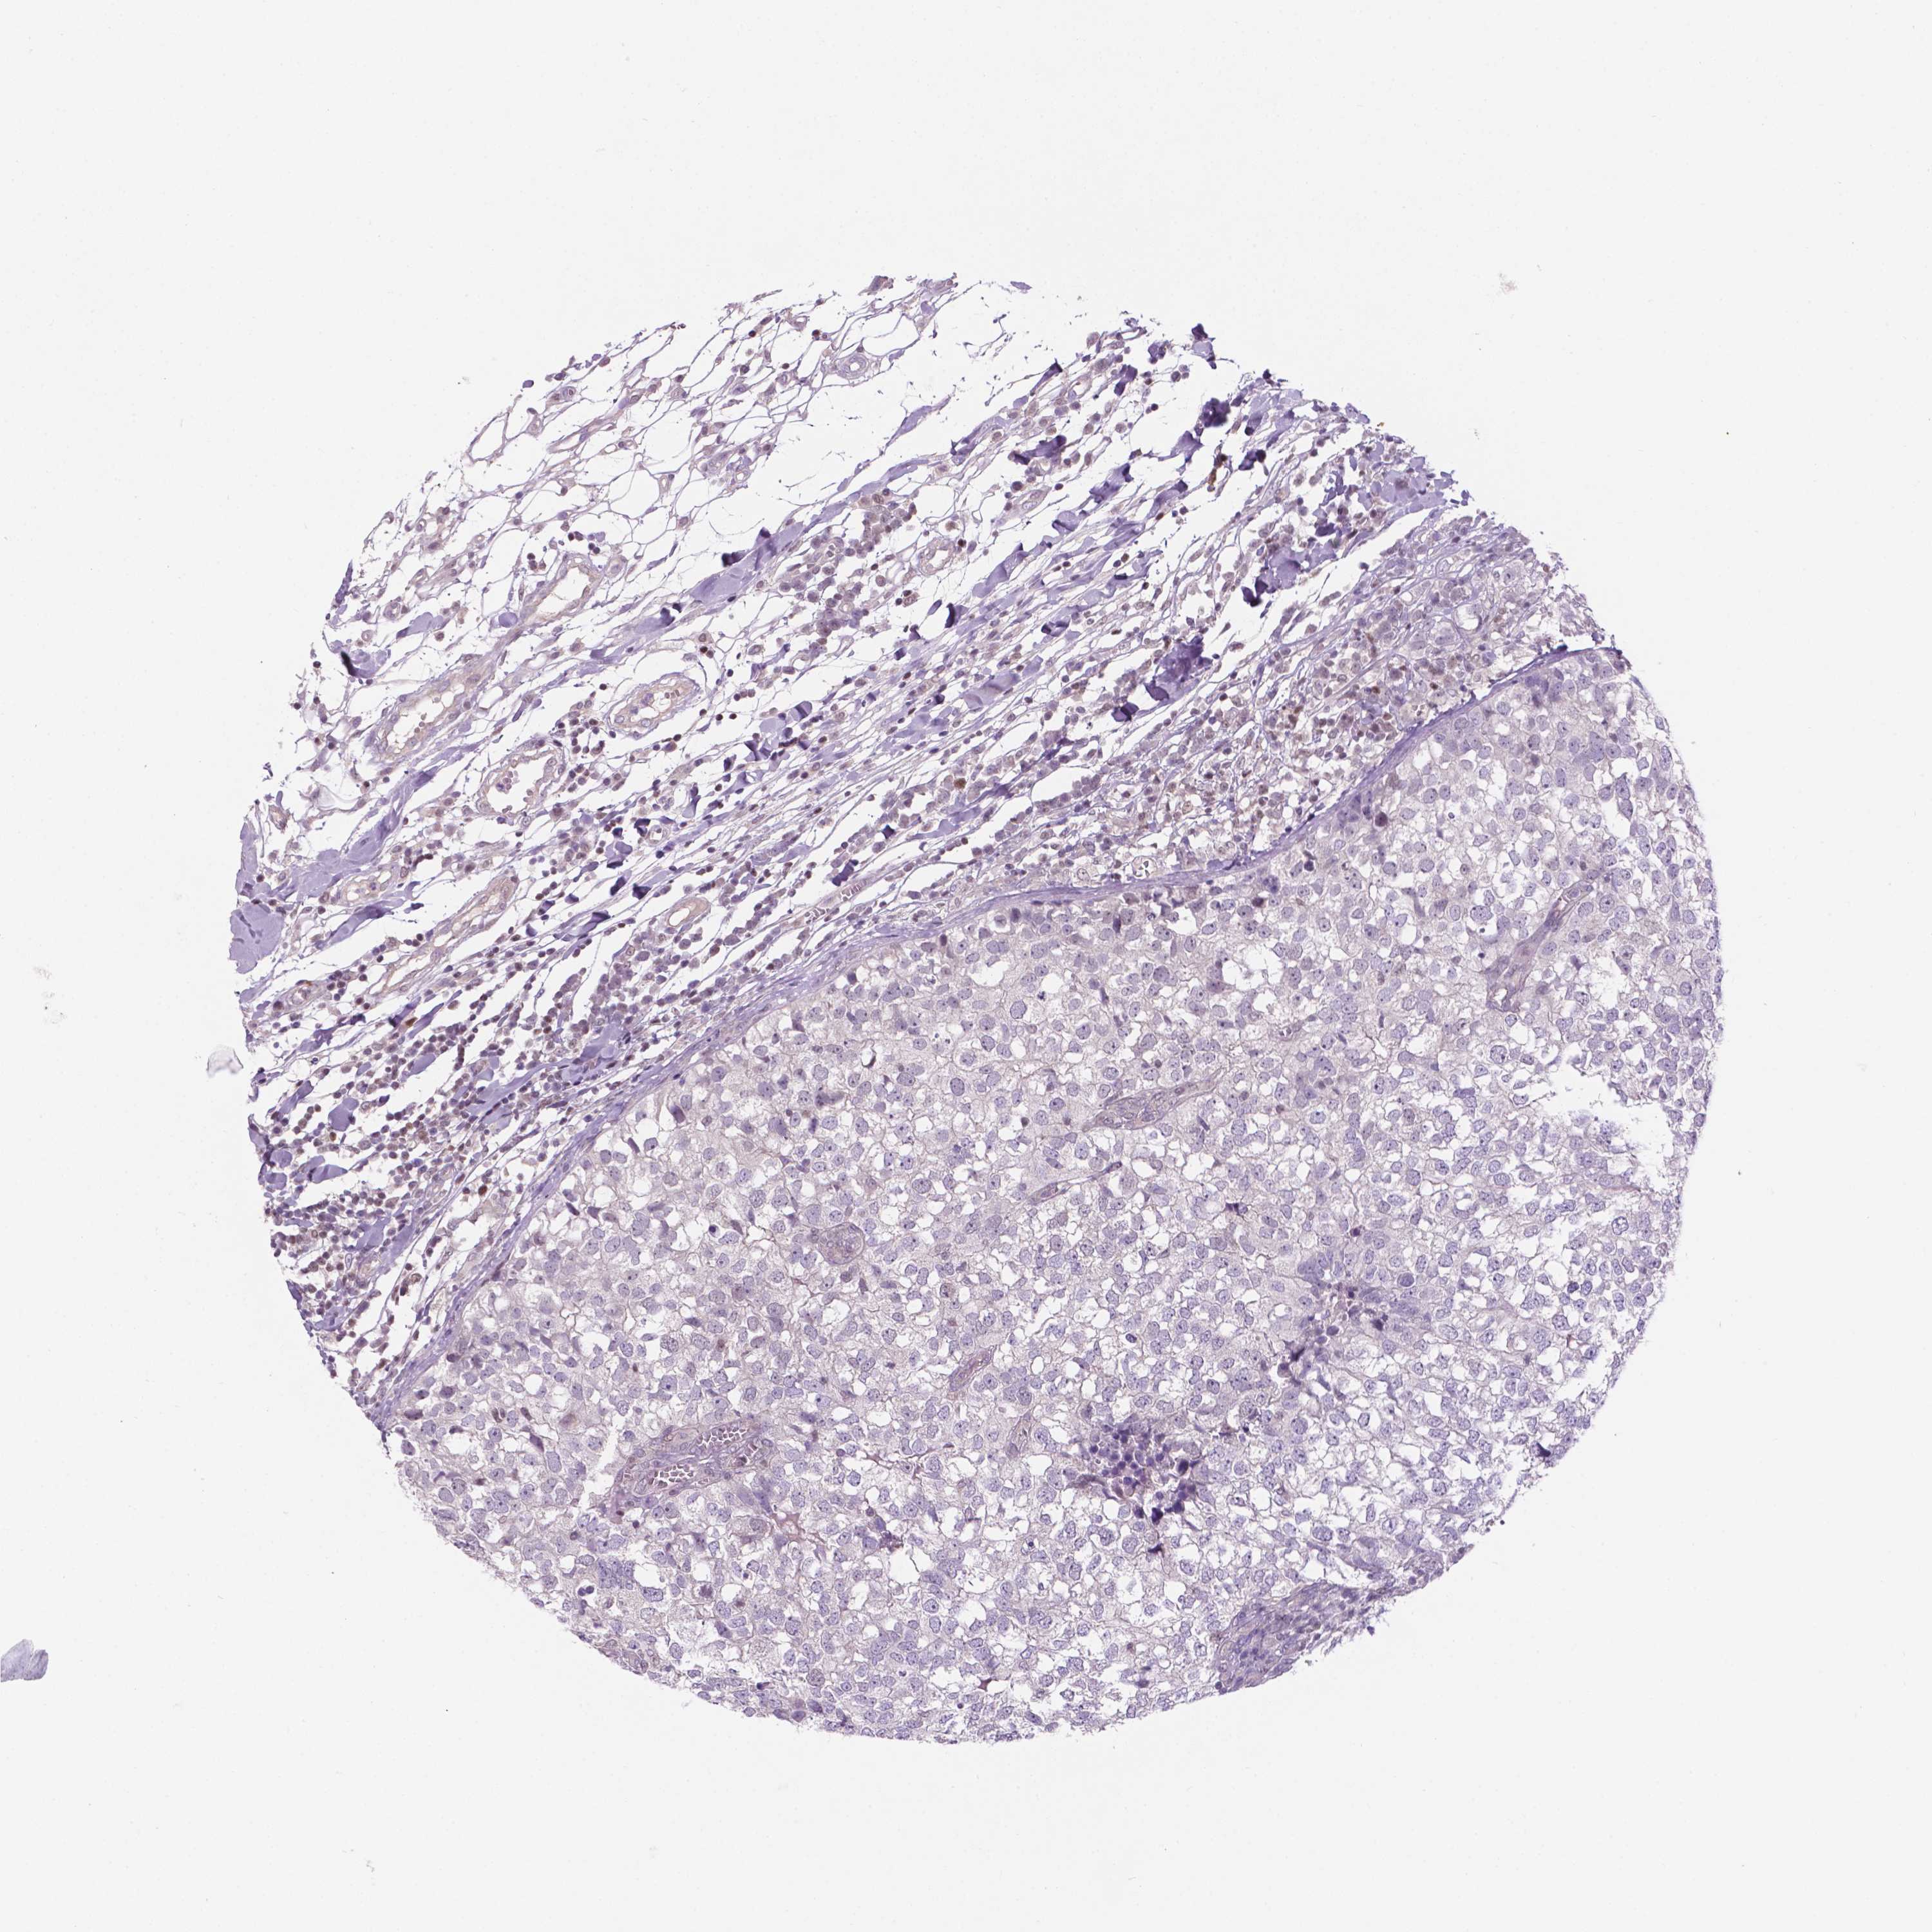

CANCER BREAST CANCER Show tissue menu

BRCA TCGA BRCA VALIDATION PROTEIN EXPRESSION

Breast cancer

Human cancer